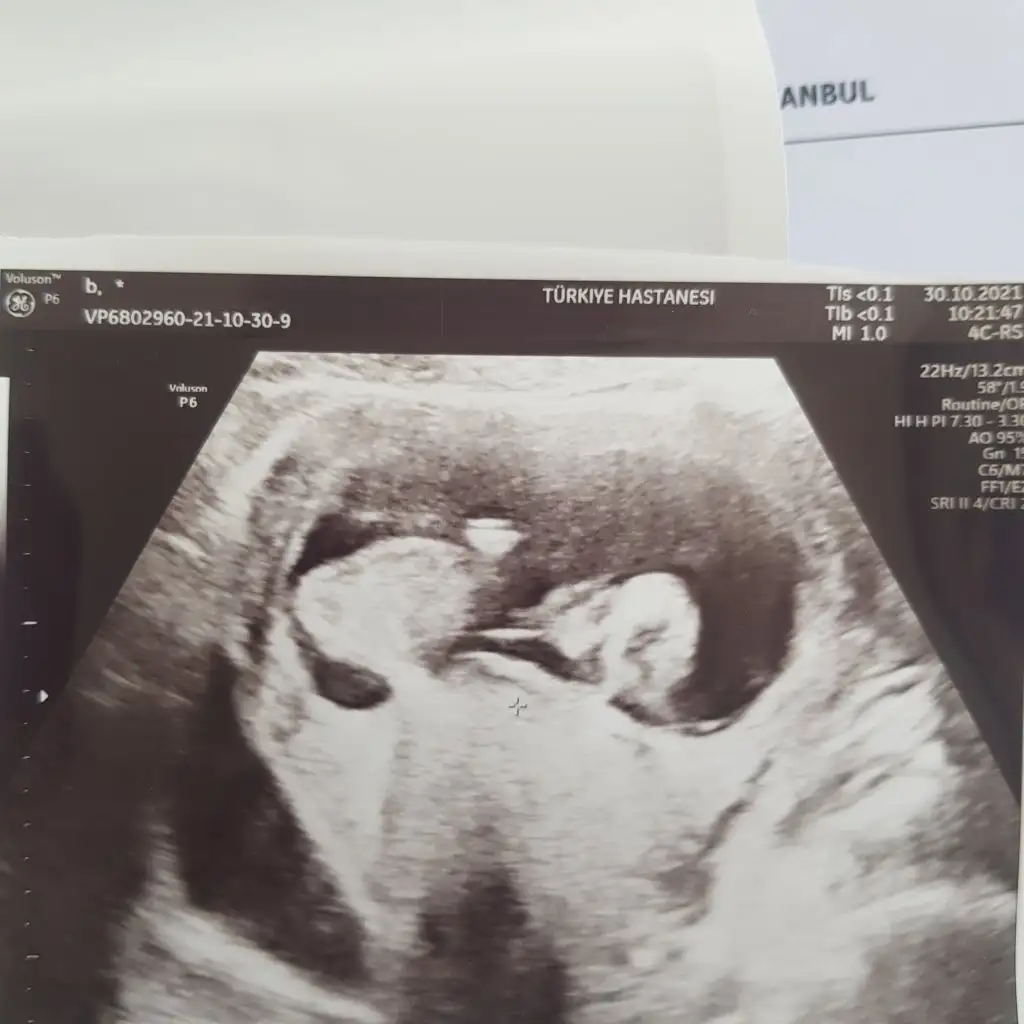

Hımm evet net değil kız mı ki acaba sizinkiSöyle bir foto var ama hic net degill

Erkek olsa gerek canım pipi orda duruyor